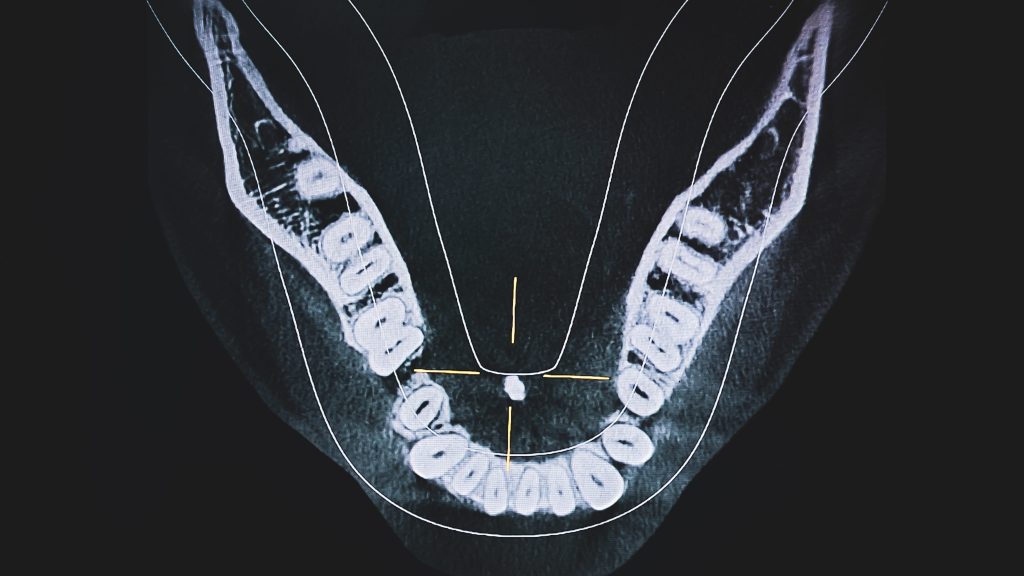

3D Imaging

Precision You Can See

At SFIOS, we use advanced Cone Beam CT (CBCT) imaging to create detailed 3D views of your teeth, jawbone, joints, and surrounding anatomy. This technology provides far more information than traditional x-rays, allowing us to diagnose accurately and plan treatment with unmatched precision.

Why It Matters

3D imaging is essential for:

• Planning dental implants and jaw surgery

• Evaluating impacted teeth or root positions

• Diagnosing TMJ disorders or bone lesions

• Assessing bone quality and sinus anatomy

• Safely navigating complex anatomical structures